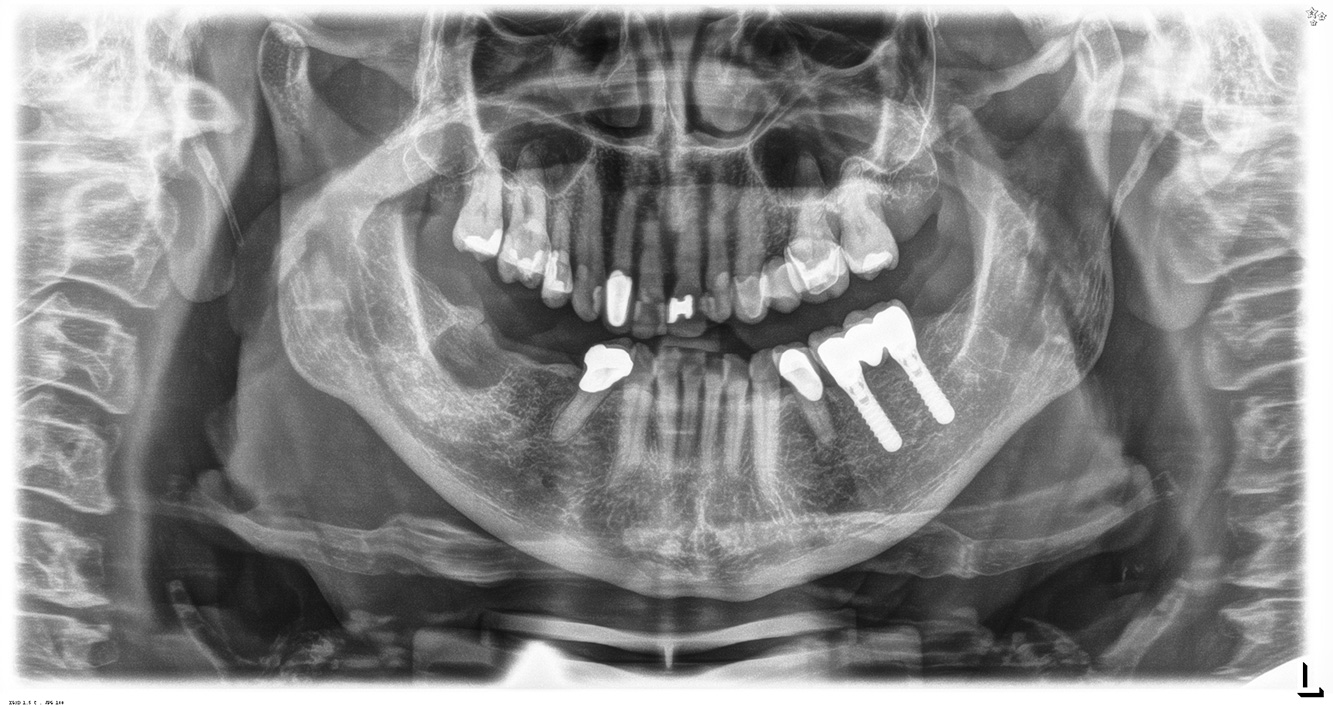

The healthy patient with pre-existing periodontal disease & peri-implantitis

Paciente sana con enfermedad periodontal previa